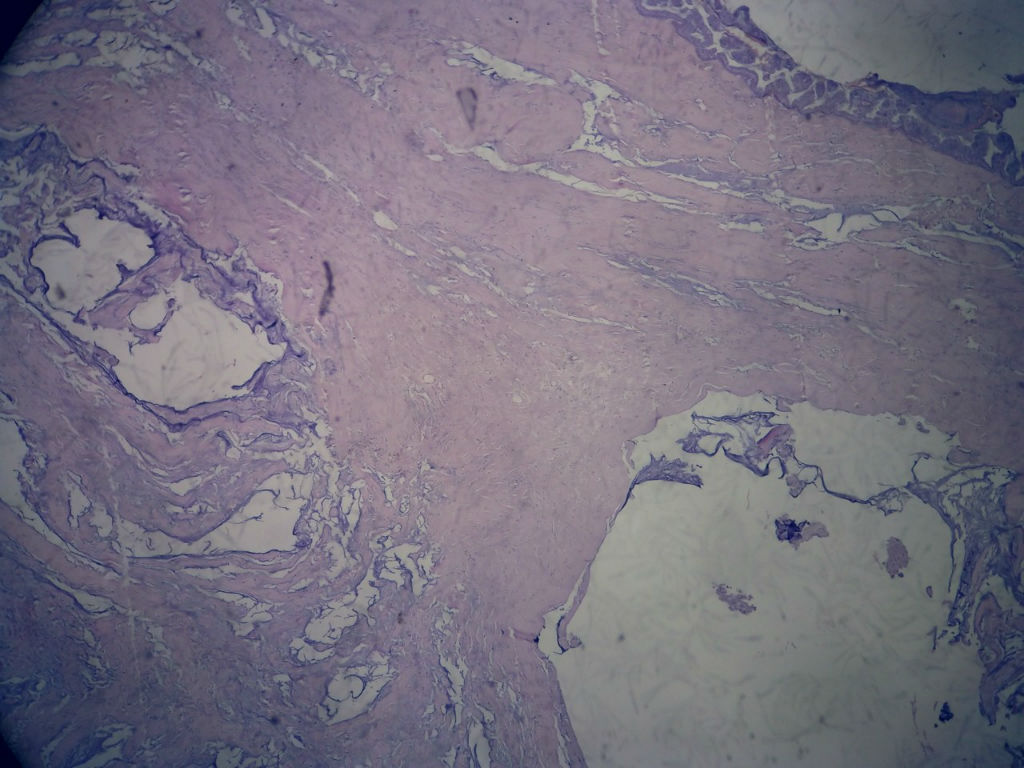

女,80岁,阑尾区肿块。

送检为不规则组织多块,粘滑,解剖结构辨认不清。术中探查双侧卵巢无异常。

• 女,80岁,阑尾区肿块。图3

图3

阑尾粘液性肿瘤,癌的可能性大

粘液长在肌层,而且漂浮着可疑上皮细胞,最大可能粘液腺癌。